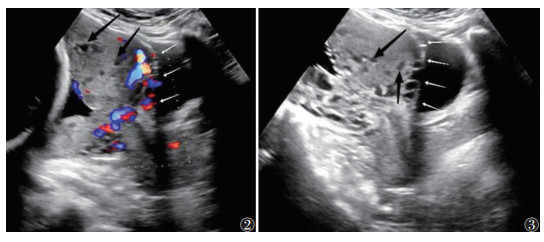

① 胎盘陷窝:胎盘实质内呈多个大小不等、形态不规则的无回声区,CDFI示血流融合成片,呈泥沙样、沸水征;②子宫-胎盘交界面异常:胎盘与子宫肌层之间的低回声带消失,子宫肌层变薄(厚度<1 mm),膀胱线中断;③子宫轮廓异常:胎盘组织使子宫轮廓扭曲,形成隆起状外观;④外生性包块:胎盘组织突出子宫浆膜层;⑤子宫-膀胱交界面桥接血管:子宫-膀胱交界面异常血流信号,血管从胎盘延伸,穿过子宫肌层,延伸至子宫浆膜外,达膀胱或其他器官,常垂直于子宫肌层[5](图 2,3)。

| 注:图2患者,女,33岁,经腹超声检查示胎盘发生植入,胎盘实质内可见大小不等无回声区(黑箭),胎盘后方子宫肌层消失,子宫-膀胱交界面异常血管,子宫浆膜- 膀胱线连续性中断(白箭)。图3患者,女,32岁,经腹超声检查示孕晚期胎盘发生植入,胎盘实质内可见大小不等无回声区,胎盘内血窦形成(黑箭),胎盘后方透明带消② ③失,子宫浆膜-膀胱线连续性中断(白箭) 图 2-3 剖宫产瘢痕处妊娠(CSP)患者超声图像 |

2 结果图 2,3剖宫产瘢痕处妊娠(CSP)患者超声图像注:图 2患者,女,33岁,经腹超声检查示胎盘发生植入,胎盘实质内可见大小不等无回声区(黑箭),胎盘后方子宫肌层消失,子宫-膀胱交界面异常血管,子宫浆膜-膀胱线连续性中断(白箭)。图 3患者,女,32岁,经腹超声检查示孕晚期胎盘发生植入,胎盘实质内可见大小不等无回声区,胎盘内血窦形成(黑箭),胎盘后方透明带消失,子宫浆膜-膀胱线连续性中断(白箭)